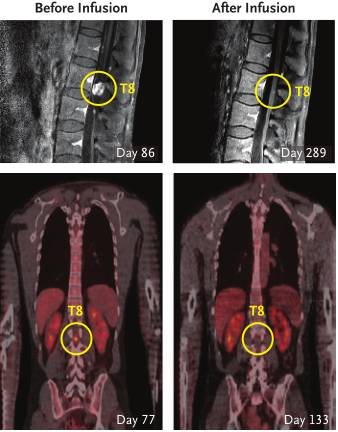

在第二次治疗中,研究人员在右侧脑室进行了10次注射。注射进行到第3次(第133天)后,患者脑内和脊柱内的所有肿瘤都变小了!在第5次注射(第190天)后,部分肿瘤消失了,剩下一部分减小了77%。在剩下的5次注射结束后,研究人员发现,患者体内的肿瘤全都消失了!在经过严格检查后,在患者体内都没有发现肿瘤的迹象。而且在治疗中几乎没有出现什么严重的副作用。